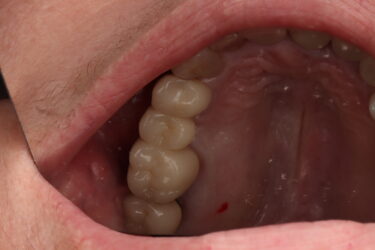

jorbrown posted an update a year ago

Case here for a maxillary partial overdenture. How do these positions look prosthetically in respect to their existing partial? I placed them as best I could. Also how far subcrestal should I am for? 1-2mm?